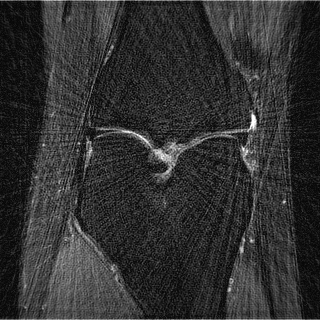

This article presents a novel undersampled magnetic resonance imaging (MRI) technique that leverages the concept of Neural Radiance Field (NeRF). With radial undersampling, the corresponding imaging problem can be reformulated into an image modeling task from sparse-view rendered data; therefore, a high dimensional MR image is obtainable from undersampled $k$-space data by taking advantage of implicit neural representation. A multi-layer perceptron, which is designed to output an image intensity from a spatial coordinate, learns the MR physics-driven rendering relation between given measurement data and desired image. Effective undersampling strategies for high-quality neural representation are investigated. The proposed method serves two benefits: (i) The learning is based fully on single undersampled $k$-space data, not a bunch of measured data and target image sets. It can be used potentially for diagnostic MR imaging, such as fetal MRI, where data acquisition is relatively rare or limited against diversity of clinical images while undersampled reconstruction is highly demanded. (ii) A reconstructed MR image is a scan-specific representation highly adaptive to the given $k$-space measurement. Numerous experiments validate the feasibility and capability of the proposed approach.